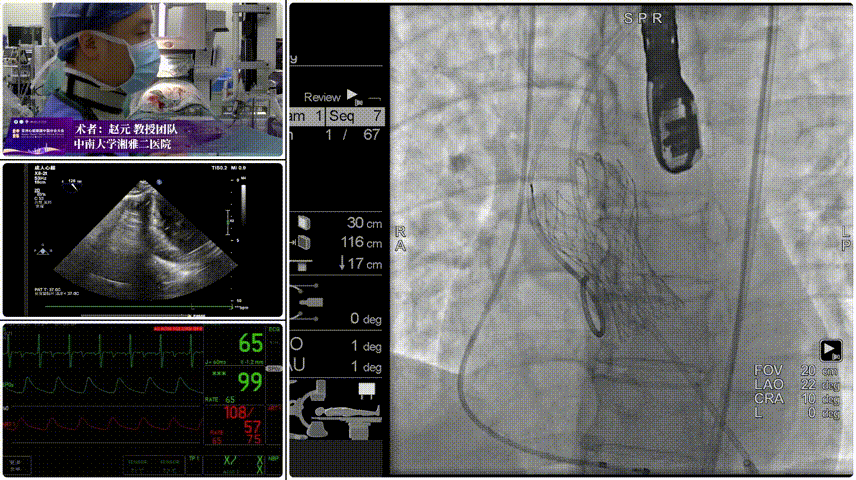

手术过程

Step 1.柔顺过弓:精湛手术操作+优异通过性能、复杂弓形无任何辅助一次通过。

Step 2.定位释放:初始高定位,使瓣膜自然下滑至理想位置。

Step 3.工作位评估:位置合适,深放以避免瓣膜开合区过度受挤压。

Step 4.稳定脱钩无位移。

Step 5.最终造影:位置合适,瓣膜形态良好,无瓣周漏。

患者压差由105mmHg降至17mmHg。

手术过程与术后转归

手术在全麻下进行,团队选择右股动脉作为主入路,凭借器械柔顺性优势一次性顺利过弓,精准抵达瓣环位置。通过多角度造影确认瓣膜同轴性良好后,逐步释放瓣膜,脱钩过程稳定无位移。术后即刻造影显示,瓣膜位置理想,无瓣周漏;超声评估提示左心室收缩功能正常,跨瓣压差显著改善,患者胸闷、气促症状明显缓解。术后 24 小时患者即可下床活动,72 小时顺利出院,未发生卒中、血管并发症、传导阻滞等不良事件。